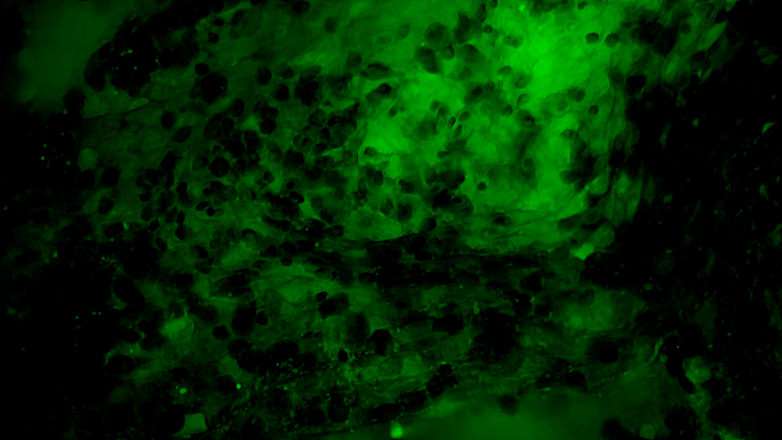

术中EndoSCell®细胞图像如下:

1.可疑组织的肿瘤细胞残留:细胞核异型性显著,分布密集且不规则。